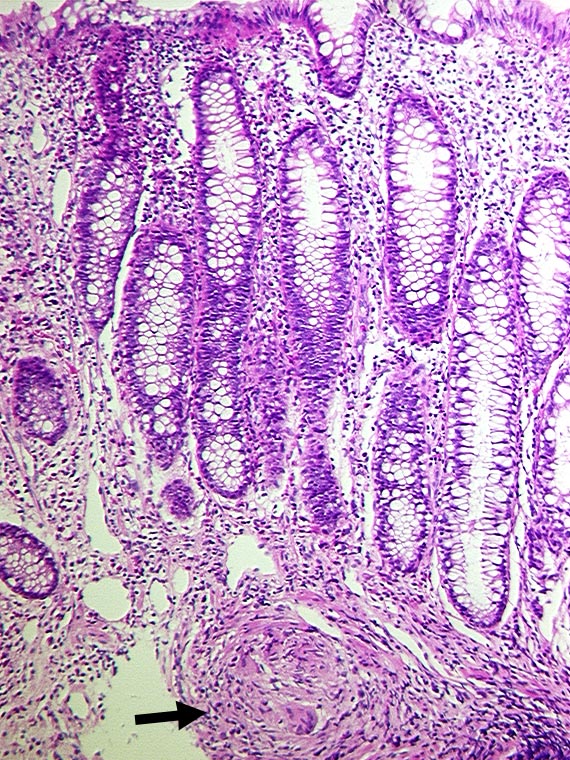

PathoPic – image database / PathoPic ID 1133 - Granulom in der Submukosa bei Morbus Crohn

Granulom in der Submukosa bei Morbus Crohn

An dieser Stelle weitgehend unauffällige Mukosa. In der Submukosa ein epitheloidzelliges ► Granulom mit einer Riesenzelle.

Fokal aktive Entzündung.

Bekannter Morbus Crohn seit 8 Jahren.